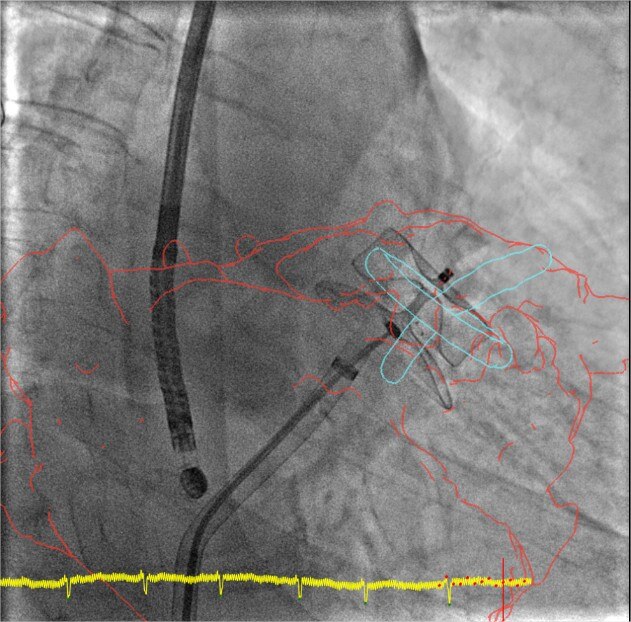

product-product-categories-Intervantional - 2016-valve_22.jpgGuiar

La fusión en 3D ayuda a guiar cada paso con confianza, desde la punción transeptal a la colocación del dispositivo. Reduzca de forma significativa la duración del procedimiento al tiempo que reduce la dosis y el medio de contraste.